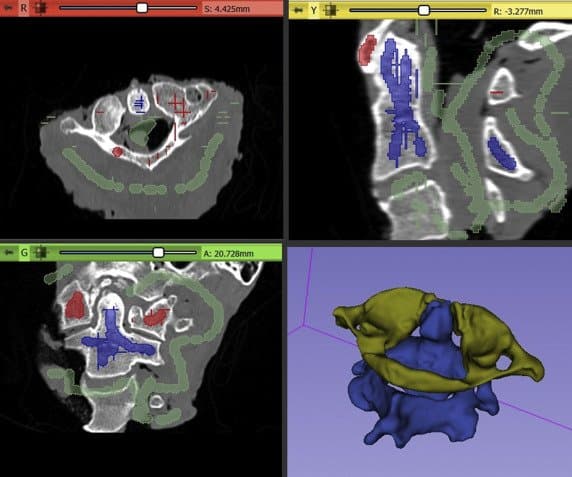

Each C1 and C2 vertebral body was individually segmented using the “paint” and semiautomated “grow-from-seeds” function in 3DSlicer.

Cylinders used during the trajectory planning before the Boolean operations were performed to create the final drill guide. The opacity of the 3D bone model was reduced to allow internal visualization.

Images show the steps used during the Boolean operations to create the final patient-specific guides (A−E) for each bone and also the 3D model that would be used later for the trajectory comparison (F).